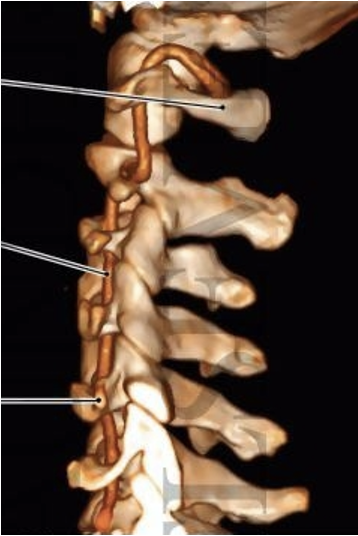

Vertebral Artery

Window between arch of C1 , superior oblique and rectus major

OCS

RC

C2

OCI

Transverse Process - C1

Arch of C1